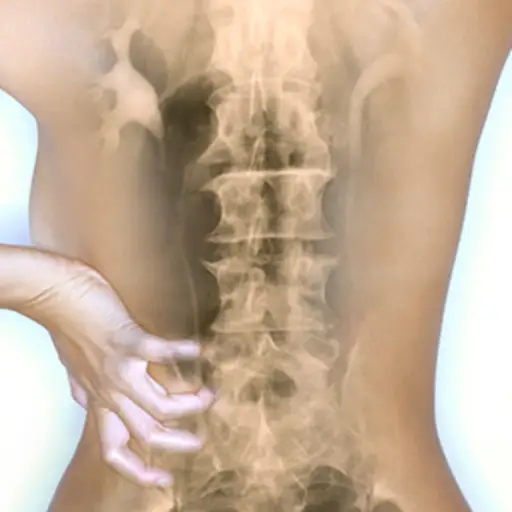

误解5:强直性脊柱炎总是会导致脊柱融合

事实:强直性脊柱炎的特征在于骶髂关节炎症,并且通常是脊柱的关节。随着疾病的进展骨刺可以形成在严重的情况下,可能会发生完全的脊柱融合,迫使脊柱形成一种驼背、僵硬的姿势,称为后凸。强直性脊柱炎的治疗旨在减缓疾病的进展,减少骨刺形成和融合的机会。